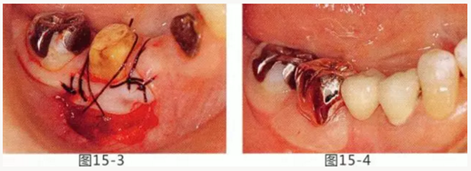

圖15-1,2 右下6近中部的頰系帶延伸到游離齦,附著齦也處于缺失狀態(tài)。如果在這個狀態(tài)下進行修復,會使清潔變得困難,容易引發(fā)牙齦萎縮。

圖15-3 切除系帶。為了獲得附著齦,進行游離齦移植。

圖15-4 手術完成6個月后,佩戴修復體時的狀態(tài)。